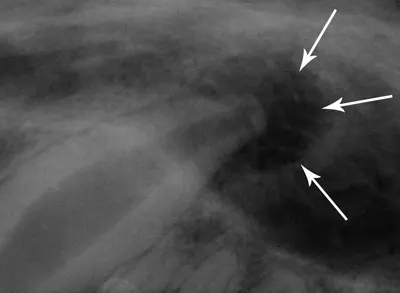

However, radiographs often reveal a small, regular widening of the periodontal space at the apex of the maxillary canines (Figure 1). This common artifact is known as a chevron effect, summation effect, or penumbra. Although this may appear to be a periapical lesion, it is differentiated from a pathologic abnormality because it is regular and v-shaped, as opposed to irregular and round (Figure 2).

Figure 1: The small, regular, v-shaped widening of the periodontal space at the apex of this maxillary canine is an artifact known as the chevron effect (arrows).